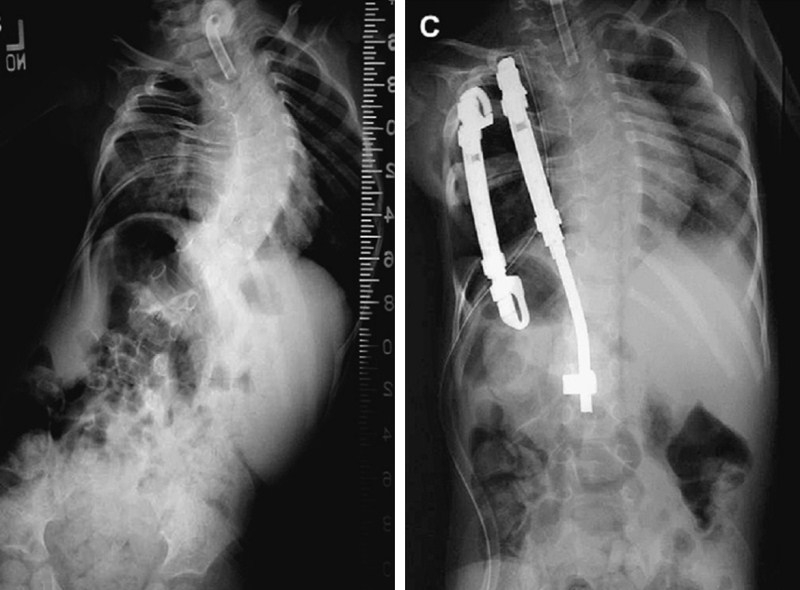

图4 A:EOS患儿术前冠状面全脊柱正位X片,左侧胸廓发育不全;B:左侧VEPTR肋骨撑开术,间接纠正脊柱畸形,以维持肺的发育